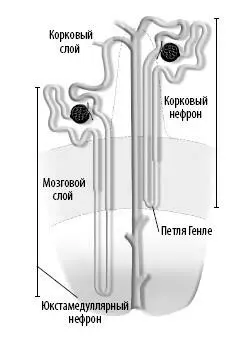

Каждая почка содержит около миллиона крошечных структур под названием «нефроны». Сами нефроны состоят из двух частей: почечного тельца и канальца. По своему расположению нефроны делятся на корковые (кортикальные) и юкстамедуллярные.

У корковых нефронов более короткие петли Генле, чем у юкстамедуллярных.